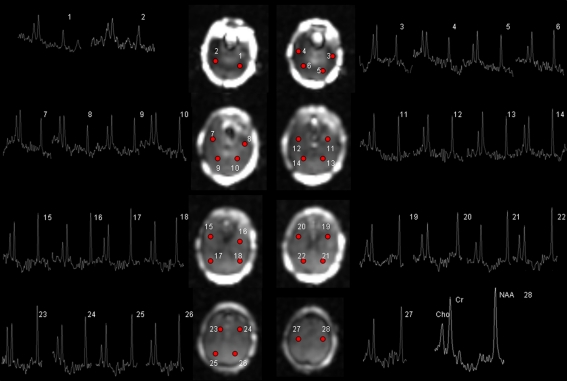

Fig. 1.

Raw 3D EPSI with representative spectra from a TLE-MTS patient with a right sided focus. All displayed spectra passed the automated quality control. Spectrum 28 has been enlarged and the peaks of the main metabolites are labelled. NAA N-acetyl-aspartate, Cr creatine/phosphocreatine, Cho choline compounds